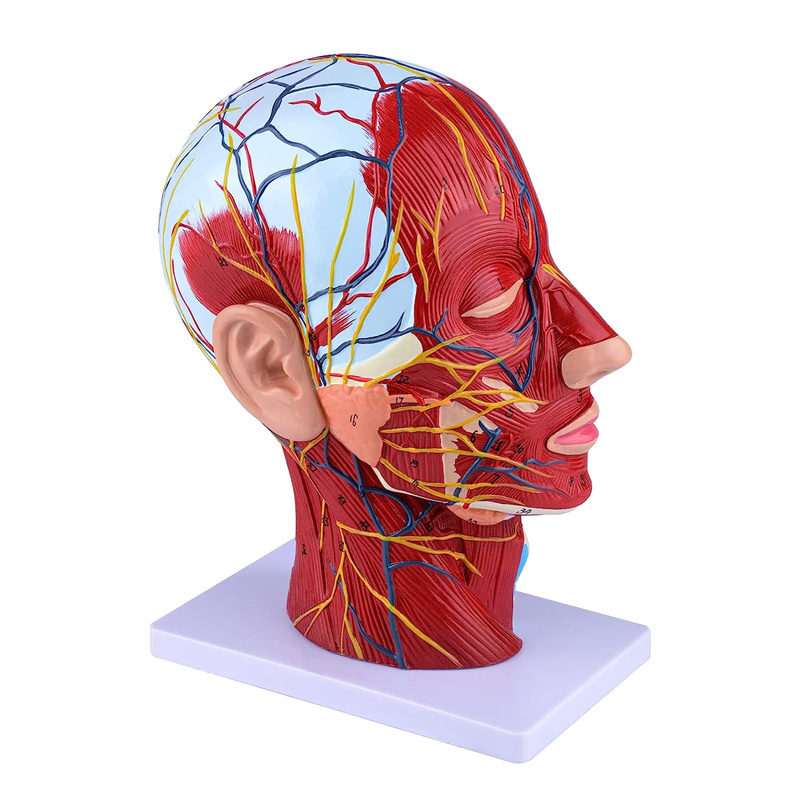

| Características | O modelo mostra a morfologia local dos lados interno e externo da seção sagital mediana da cabeça e pescoço, bem como as estruturas dos vasos sanguíneos e nervos, e há 84 partes indicando sinais no total. |

【Modelo superficial do músculo neurovascular】 Números altamente detalhados, marcados e destacáveis, aprofundar o entendimento dos músculos superficiais, vasos, nervos e as estruturas internas da cabeça e pescoço. Artéria vermelha, azul-veia, nervo amarelo.

【Apresenta】 mostra os músculos superficiais da face exposta; os vasos sanguíneos superficiais e os nervos do rosto e do couro cabeludo; as estruturas internas da glândula parótida e do trato respiratório superior; A estrutura de seção transversal sagital da coluna cervical.

Este modelo mostra detalhes do pescoço da cabeça direita e da seção sagital média do humano. incluindo o superficial

músculos da face exposta; os vasos sanguíneos superficiais e os nervos do rosto e do couro cabeludo; as estruturas internas

da glândula parótida e trato respiratório superior; A estrutura de seção transversal sagital da coluna cervical.

O modelo mostrou a morfologia local das seções sagitais mediais e laterais da cabeça e pescoço e suas estruturas vasculares e nervosas, com um total de 100 indicadores do local.

Este modelo é um modelo muscular neurovascular superficial grande e pescoço natural, um componente 1, mostrando os detalhes da cabeça e pescoço direito humano e seção sagital mediana, incluindo os músculos superficiais expostos da face, vasos superficiais do rosto e do couro cabeludo, nervos e a estrutura medial da glândula parótida e do trato respiratório superior, e a estrutura da seção sagital da coluna cervical